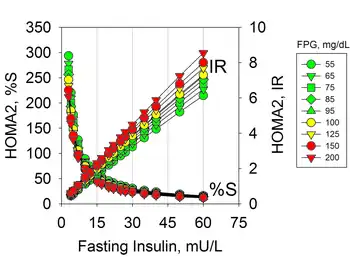

Fasting Insulin

Hyperinsulinemia due to insulin resistance may occur in individuals with normal glucose levels and therefore is not diagnosed with usual tests. Hyperinsulinemia precedes prediabetes and diabetes that are characterized by hyperglycemia.[16] Insulin resistance can be diagnosed by measures of plasma insulin, both fasting or during a glucose tolerance test.[17][18] The use of fasting insulin to identify patients at risk has been proposed, but is currently not commonly used in clinical practice.[19]

The implications of hyperinsulinemia is the risk of comorbidities related to diabetes that may precede changes in blood glucose,[20][21][16] including cardiovascular diseases.[22][23][24]